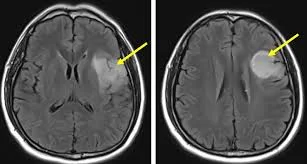

Πώς γίνεται η διάγνωση (MRI, EEG) και τι μπορεί/δεν μπορεί να δείξει η MRI;

Η MRI είναι βασική διαγνωστική εξέταση, αλλά δεν μπορεί πάντα να ξεχωρίσει αξιόπιστα χαμηλού από υψηλού βαθμού γλοιώματα, χωρίς ιστολογική και μοριακή τεκμηρίωση.

• MRI εγκεφάλου (με/χωρίς σκιαγραφικό): αναδεικνύει την έκταση της βλάβης, χαρακτηριστικά και σχέση με λειτουργικές περιοχές.

Στην κλινική πρακτική, η απουσία έντονης πρόσληψης σκιαγραφικού συχνά “υποδηλώνει” χαμηλότερο βαθμό γλοιώματος, αυτό όμως δεν είναι απόλυτο. Η τελική τεκμηρίωση βασίζεται στη συνολική εικόνα και σε ιστολογική/μοριακή διάγνωση, όταν ενδείκνυται.

Όχι. Η απουσία έντονης πρόσληψης σκιαγραφικού συχνά συσχετίζεται με γλοιώματα χαμηλότερου βαθμού, αλλά αυτό δεν είναι απόλυτο. Η ασφαλέστερη εκτίμηση προκύπτει από το σύνολο των ευρημάτων και ιστολογική/μοριακή επιβεβαίωση.